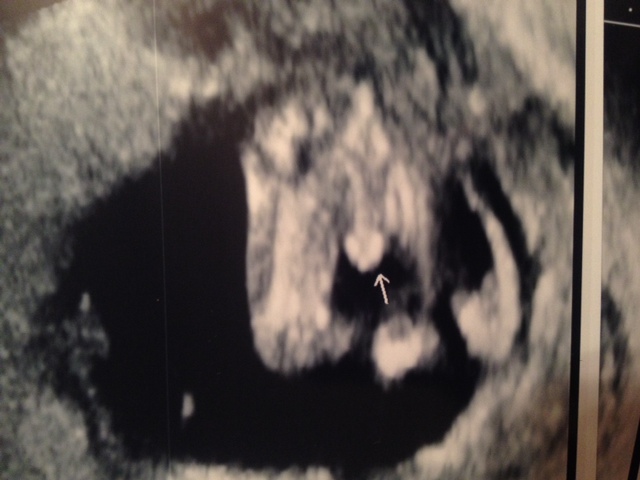

Skull theory from the front?

I have been MIA lately. Between this all day sickness and DD being in Kindergarten and me volunteering almost everyday then coming home and having to play housewife I forgot what the internet was. I had my 12 week appointment last week. They couldn't find the heartbeat so I got another ultrasound and the baby was perfectly fine. He printed me off a picture of the babys face front on. I didn't know if there was a skull theory for the front of the face ... just in case I am going to upload it. If not I have my 13 week NT scan on Wednesday and am hoping the baby cooperates and gives us a good potty shot!Attachment 15191